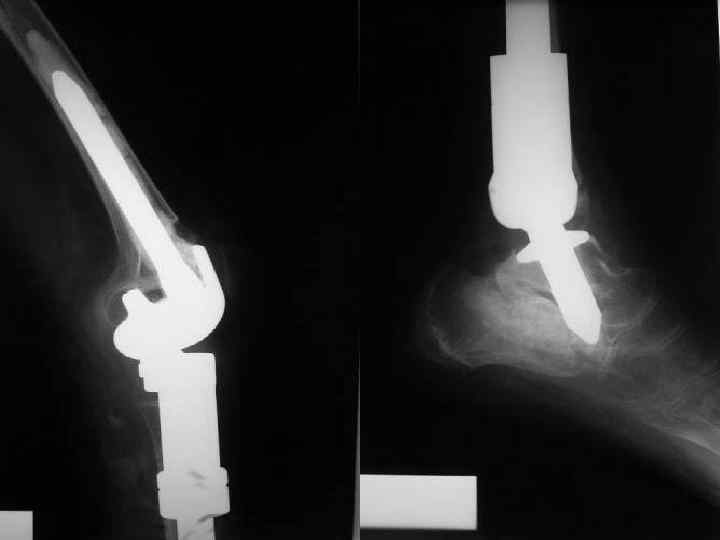

Рентгенограммы нижней конечности после удаления опухоли и эндопротезирования. Большеберцовая кость и два сустава – коленный и голеностопный замещены индивидуальным удлиняющимся эндопротезом.

Тот же пациент. Рентгенограмма плеча после удаления всей плечевой кости с опухолью и её замещения индивидуальным раздвижным эндопротезом плечевой кости с замещением плечевого и локтевого суставов. Пружинка – составная часть раздвижного механизма эндопротеза.